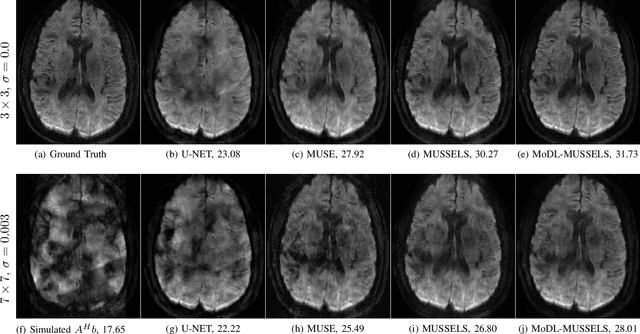

Abstract:We propose a model-based deep learning architecture for the correction of phase errors in multishot diffusion-weighted echo-planar MRI images. This work is a generalization of MUSSELS, which is a structured low-rank algorithm. We show that an iterative reweighted least-squares implementation of MUSSELS resembles the model-based deep learning (MoDL) framework. We propose to replace the self-learned linear filter bank in MUSSELS with a convolutional neural network, whose parameters are learned from exemplary data. The proposed algorithm reduces the computational complexity of MUSSELS by several orders of magnitude while providing comparable image quality.